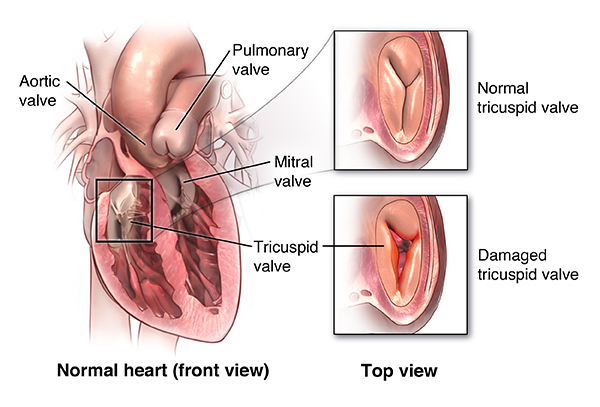

Value added benefits of the Tricuspid Valve Replacement:

Ø Doctor consultation charges

Ø Lab tests and diagnostic charges

Ø Room charges inside hospital during the procedure

Ø Surgeon Fee

Ø Nursing charges

Ø Hospital surgery suite charges

Ø Anesthesia charges

Ø Routine medicines and routine consumables (bandages, dressings etc.)

Ø Food and Beverages inside hospital stay for patient and one attendant.

Extra benefits:

ü Interpreter

ü Visa assistance

Ø Site tourism of the city

Ø Follow up with the doctor

Ø Airport pick up and drop

Ø Free online consultation with the doctor

Ø Priority appointments with the doctor

Ø Room upgrade from sharing to private